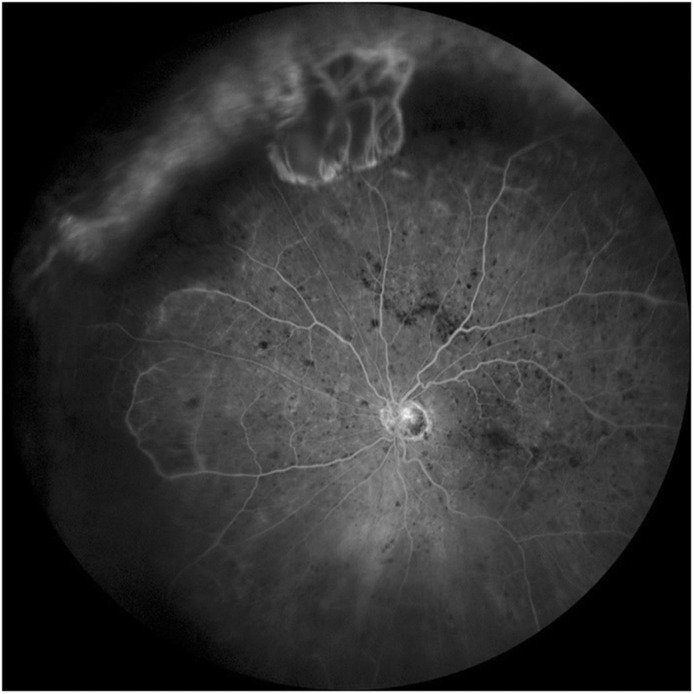

Case presentation: We report a rare case of a 79-year-old woman who underwent 360° buckling surgery with cerclage for retinal detachment 10 years ago. Although the initial surgery successfully reattached the retina, she later developed a complication characterized by peripheral retinal ischemia and secondary neovascular glaucoma.